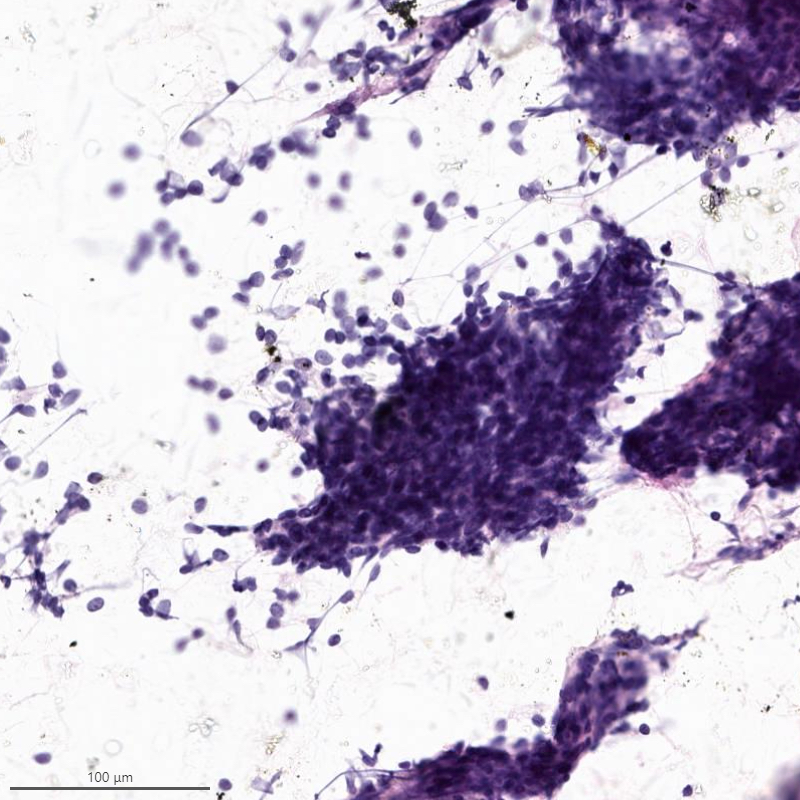

Cytology description

- Resembles benign endometrial stromal cells

- Moderate to marked cellularity composed of single cells and clusters of bland cells with scant cytoplasm, small round to spindle nuclei with fine chromatin (Acta Cytol 2007;51:461)

- Interspersed delicate blood vessels may be present

- Distinction between low grade endometrial stromal sarcoma and endometrial stromal nodule cannot be made based on cytology, as it requires evaluation of the tumor myometrium interface

- Distinction between low grade endometrial stromal sarcoma and other monomorphic spindle cell neoplasm is difficult on cytology, especially without immunohistochemistry